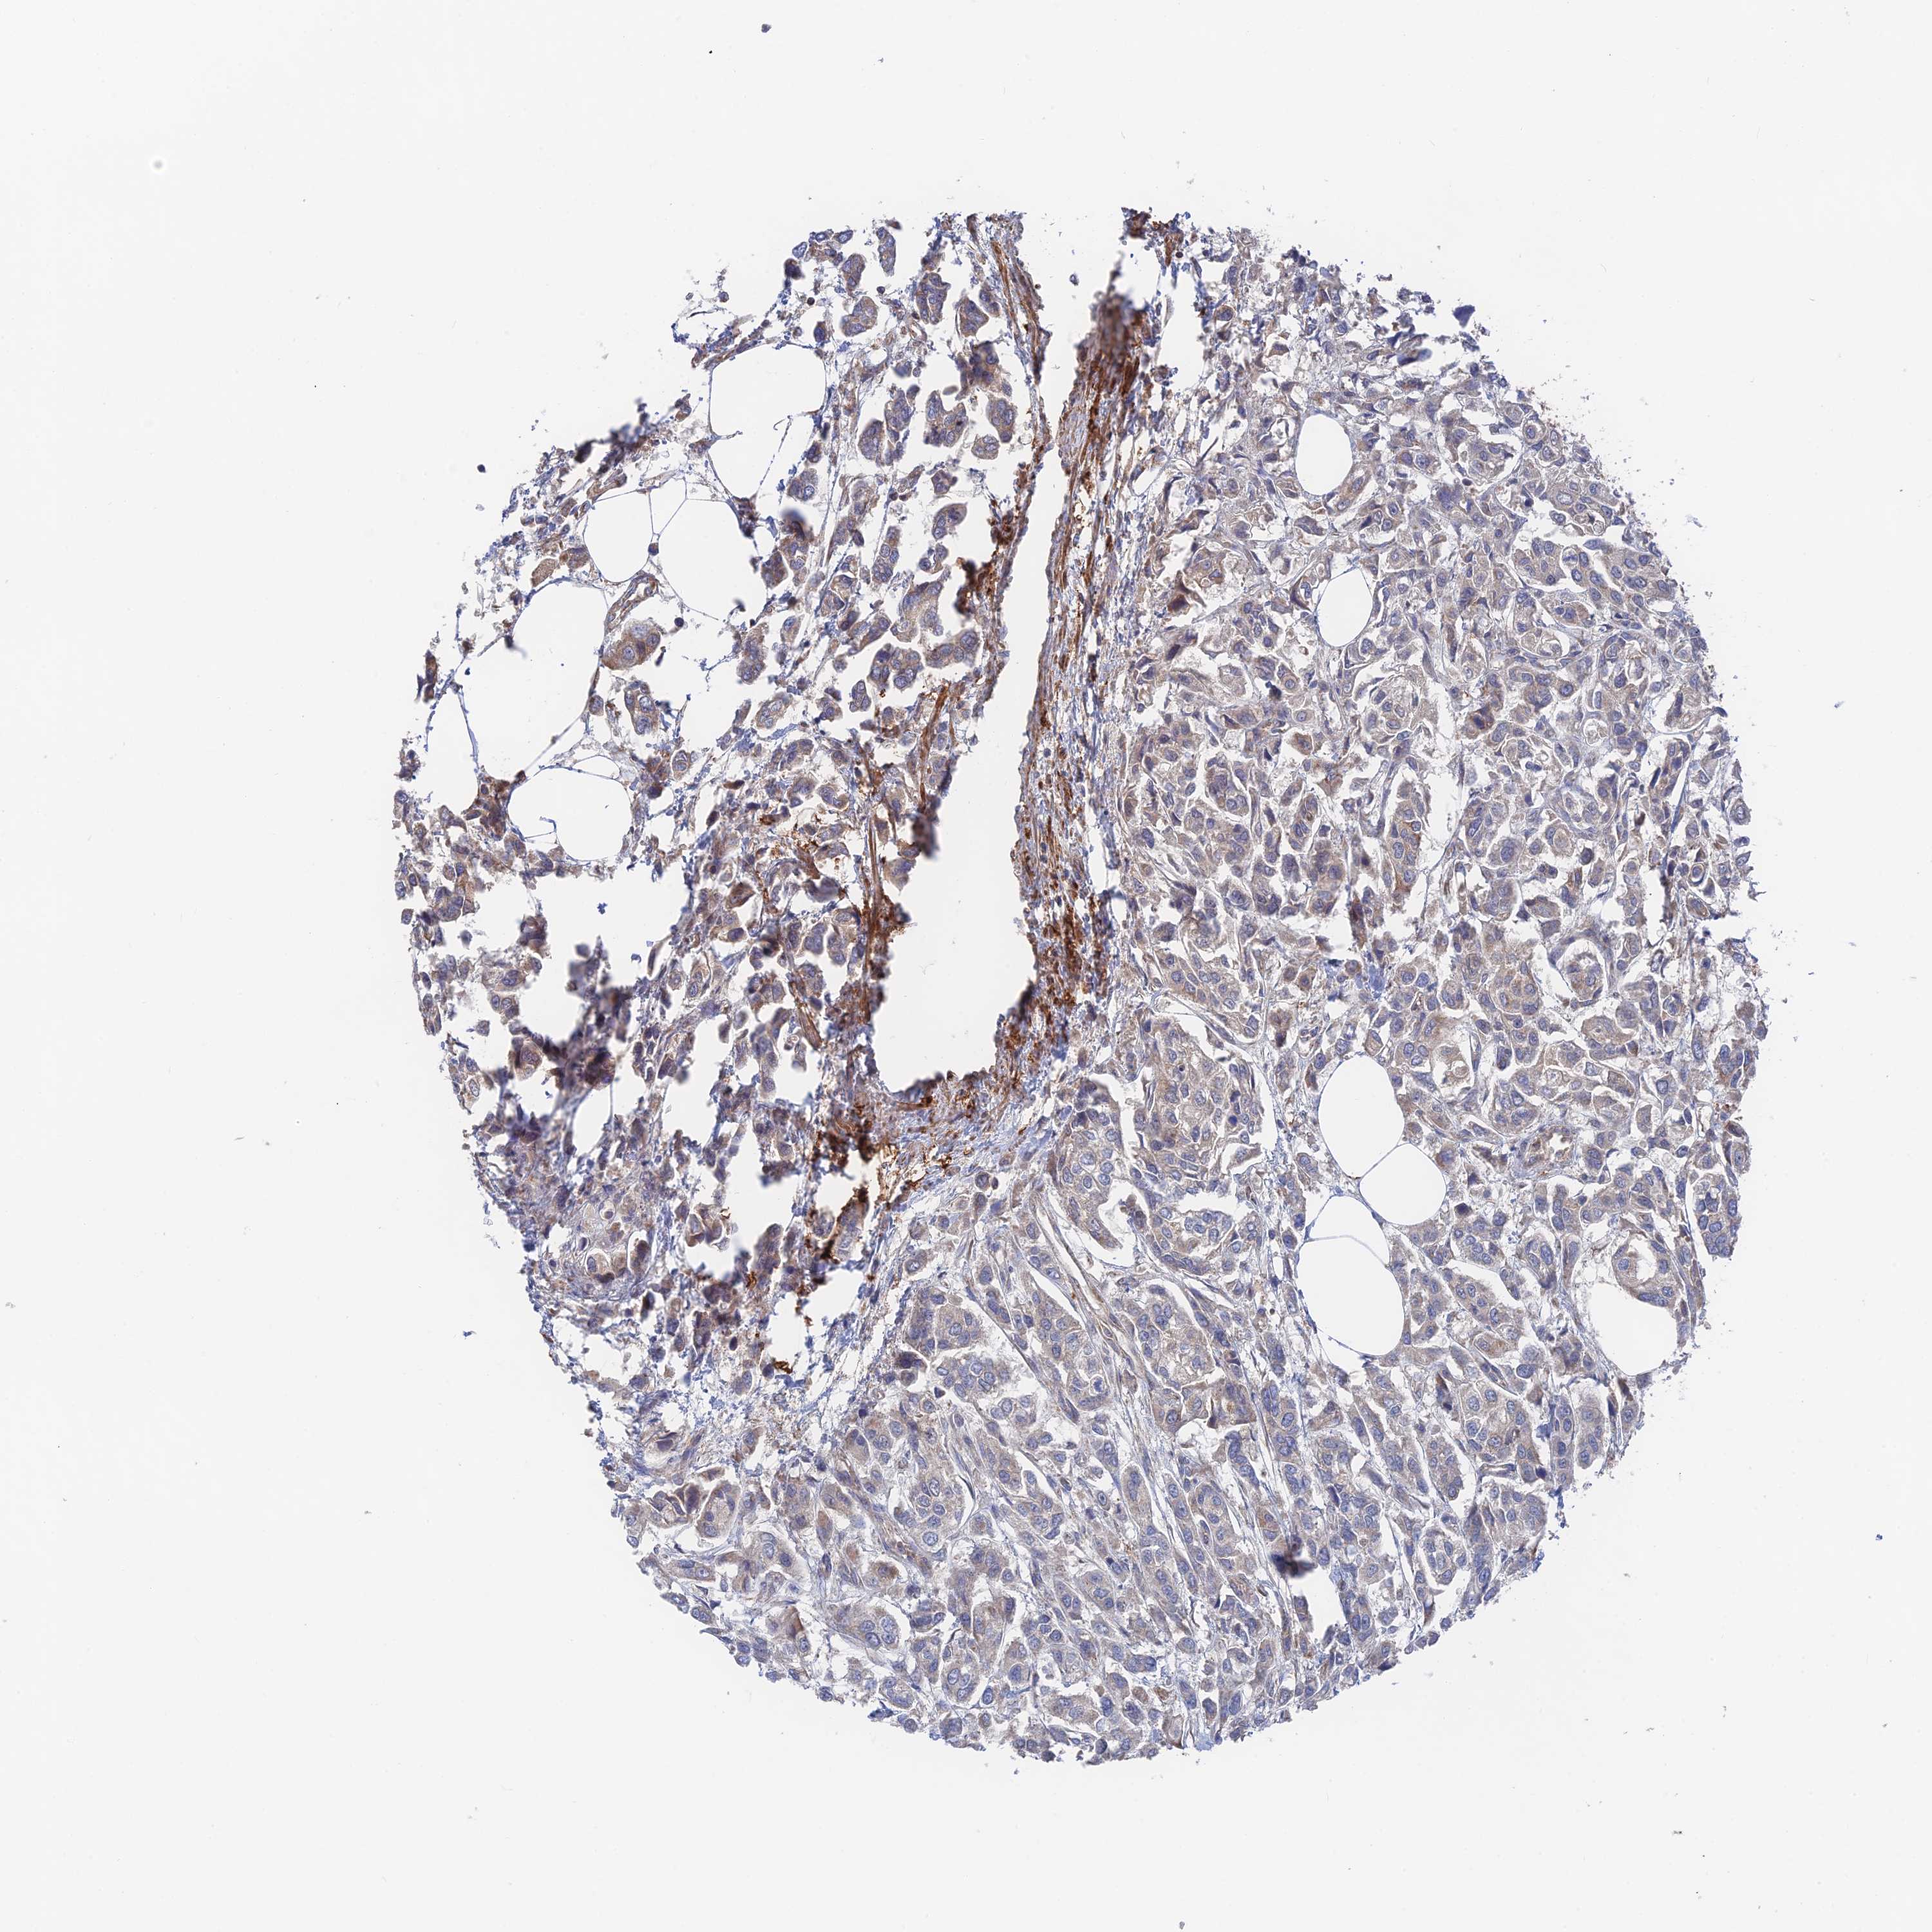

UROTHELIAL CANCER - Protein expressioni

A mouse-over function shows sample information and annotation data. Click on an image to view it in a full screen mode. Samples can be filtered based on level of antibody staining by selecting one or several of the following categories: high, medium, low and not detected. The assay and annotation is described here.

Note that samples used for immunohistochemistry by the Human Protein Atlas do not correspond to samples in the TCGA dataset.

Antibody stainingi

Antibody staining in the annotated cell types in the current human tissue is reported as not detected, low, medium, or high, based on conventional immunohistochemistry profiling in selected tissues. This score is based on the combination of the staining intensity and fraction of stained cells.

Each image is clickable and will lead to virtual microscopy that enables deeper exploration of all samples and also displays staining intensity scores, fraction scores and subcellular localization as well as patient and tissue information for each sample.

Antibody HPA043696

Staining

High

Medium

Low

Not detected

Intensity

Strong

Moderate

Weak

Negative

Quantity

>75%

75%-25%

<25%

None

Location

Nuclear

Cytoplasmic/membranous

Cytoplasmic/membranous,nuclear

Urothelial carcinoma, High grade

Urothelial carcinoma, Low grade